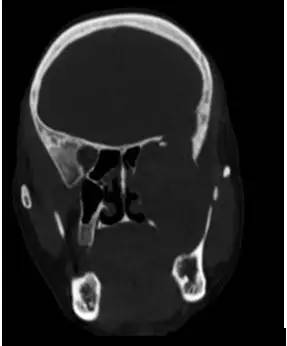

CT平扫冠状位重建

CT骨窗冠状位重建

解析:本病例为中颅窝至颞下窝沟通性病变,对周围骨质主要呈膨胀压迫性改变,伴囊变、出血。